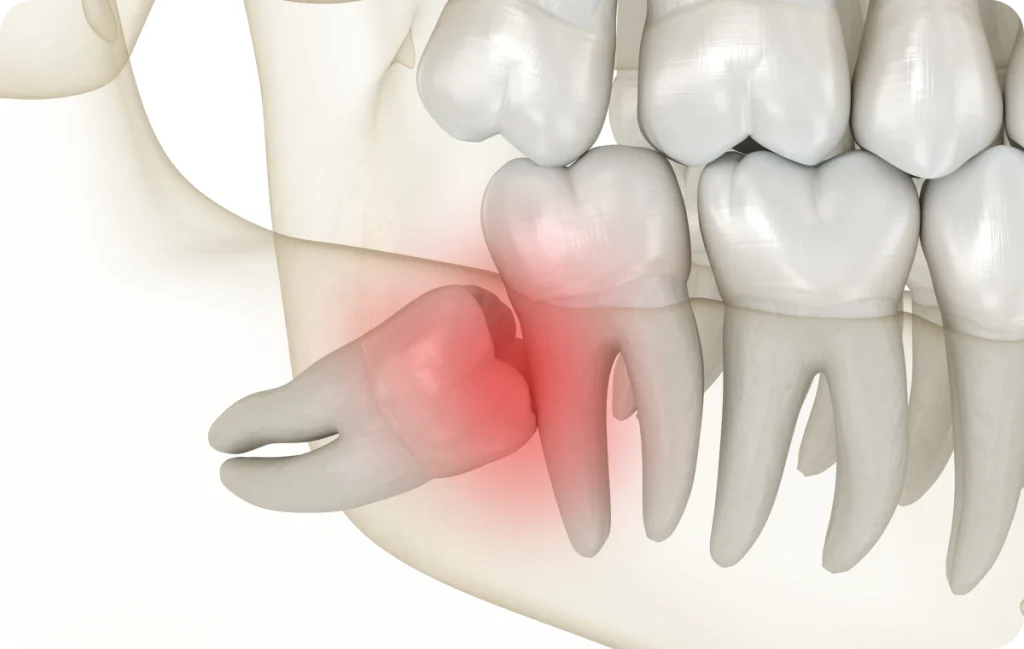

Le manque de place constitue l’une des situations les plus courantes. Lorsque l’arcade dentaire est déjà complète, l’arrivée des dents de sagesse peut être compromise. Elles peuvent alors pousser de manière inclinée ou rester bloquées sous la gencive.

Cette configuration peut rendre le nettoyage difficile et favoriser l’apparition d’inflammations locales. Une évaluation permet de déterminer si une surveillance simple est suffisante ou si une prise en charge doit être envisagée.

• Dents de sagesse partiellement sorties

Lorsqu’une dent de sagesse n’émerge que partiellement, une zone de gencive peut rester en recouvrement. Cette situation favorise l’accumulation de résidus alimentaires et de bactéries.

Une inflammation locale peut alors apparaître, accompagnée de douleurs ou d’une gêne lors de la mastication. Une attention particulière à l’hygiène et un suivi adapté permettent de limiter ces désagréments.

• Dents de sagesse incluses

Une dent de sagesse incluse reste entièrement ou partiellement enfermée dans l’os de la mâchoire. Cette situation peut rester asymptomatique pendant longtemps. Toutefois, une dent incluse peut parfois exercer une pression sur les dents voisines ou être associée à des modifications des tissus environnants.